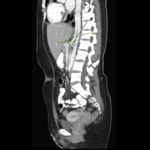

Malignant Tumors of the Small Intestine: A Case Series and Review of the Literature

Small bowel neoplasms are uncommon gastrointestinal malignancies, but their incidence has risen in recent years. The main subtypes include adenocarcinoma and neuroendocrine tumors, each accounting for approximately 40% of cases, […]